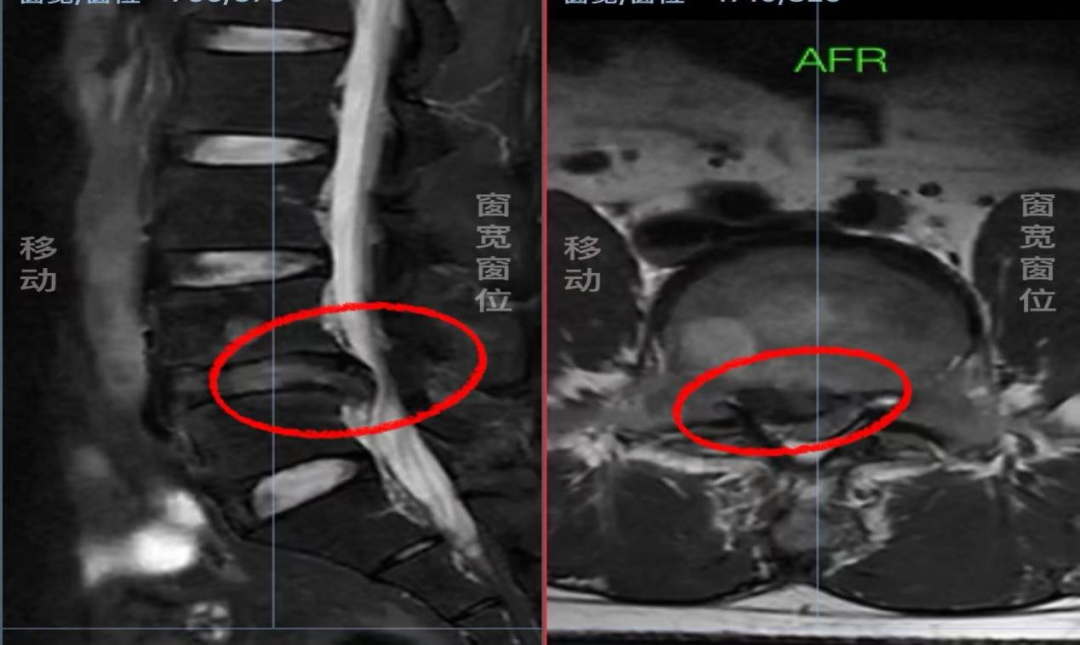

▲术前MRI影像巨大突出